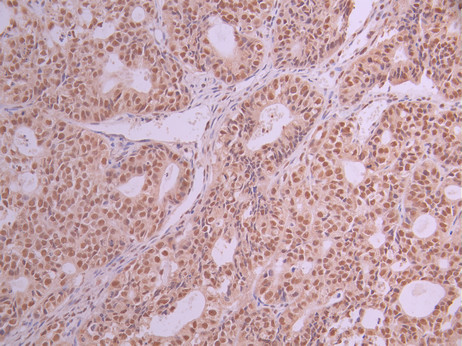

• IHC image of CSB-RA957337A0HU diluted at 1:100 and staining in paraffin-embedded human ovarian cancer performed on a Leica BondTM system. After dewaxing and hydration, antigen retrieval was mediated by high pressure in a citrate buffer (pH 6.0). Section was blocked with 10% normal goat serum 30min at RT. Then primary antibody (1% BSA) was incubated at 4°C overnight. The primary is detected by a Goat anti-rabbit polymer IgG labeled by HRP and visualized using 0.05% DAB.